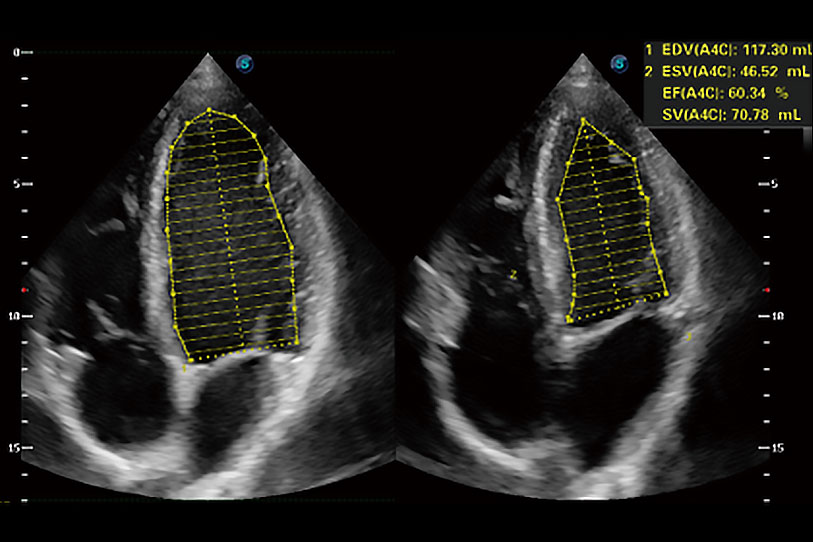

能夠基于左心室壁追蹤和辛普森法,自動(dòng)計(jì)算射血分?jǐn)?shù),支持多個(gè)可移動(dòng)點(diǎn)描跡,與手動(dòng)測(cè)量相比,極大節(jié)省了動(dòng)物醫(yī)生的時(shí)間和精力。

具備多種協(xié)議可選,同時(shí)支持17階段劃分法和專業(yè)的SE報(bào)告。

通過(guò)360度任意調(diào)節(jié)3條M型取樣線,在同一心動(dòng)周期上觀察心臟不同位置的運(yùn)動(dòng)曲線,得到準(zhǔn)確的心功能測(cè)量數(shù)據(jù),有效評(píng)估心肌運(yùn)動(dòng)及左心室功能。

當(dāng)心臟測(cè)量結(jié)果超出正常范圍時(shí),可實(shí)時(shí)預(yù)警提示動(dòng)物醫(yī)生,減少疾病漏診概率。